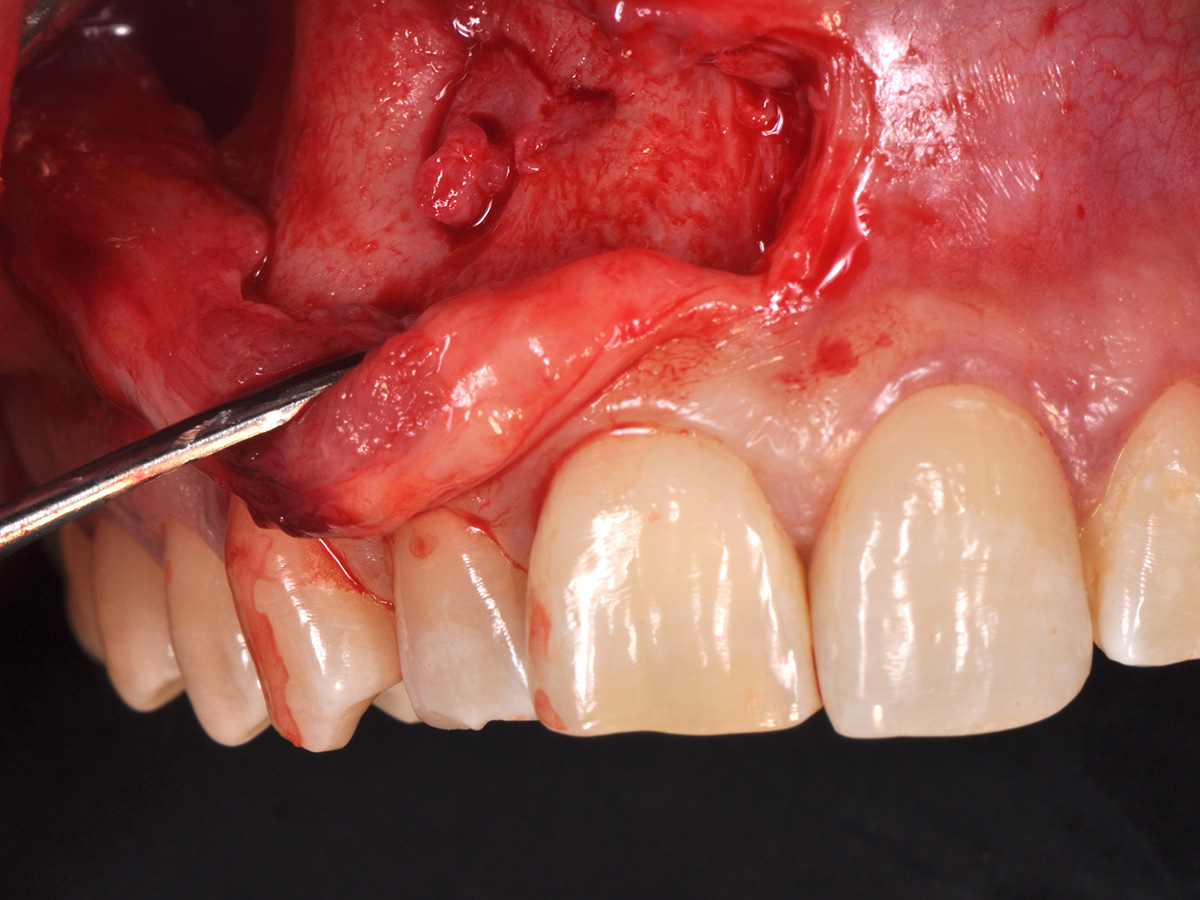

Abbildung 10

Nach vestibulärer Freilegung wurde die Zyste vollständig entfernt und zur histopathologischen Untersuchung eingesandt.

Mit der Patientin wurde der Versuch des Zahnerhaltes trotz ausgedehnter Zyste besprochen. Gleichzeitig sollte das Zystenlumen zu einer sicheren ossären Durchbauung geführt werden, um eine implantologische Sofortversorgung vorzubereiten, falls zu einem späteren Zeitpunkt eine Zahnentfernung notwendig werden sollte. In der Phase vor der geplanten Operation wurden die Wurzelkanalfüllungen an Zahn 11 und 12 durch einen Endodontologen alio loco revidiert. Die Schnittführung wurde aufgrund des bestehenden „Gummy Smile“ hoch im Vestibulum geführt – so konnte die delikate Parodontalstruktur in ihrer Form unangetastet belassen werden, um einen möglichst optimalen ästhetischen Erfolg zu erreichen (Abb. 8, 9). Nach vestibulärer Freilegung wurde die Zyste vollständig entfernt und zur histopathologischen Untersuchung eingesandt (Abb. 10). Anschließend erfolgte eine Wurzelspitzenresektion an den Zähnen 11 und 12 durch die vestibuläre ossäre Perforation (Abb. 11), gefolgt von einer ultraschallbasierten, retrograden Kanalaufbereitung und Abdichtung mit MTA. Um die knöcherne Durchbauung am Boden der Zyste osteoinduktiv zu unterstützen, wurden mit Hilfe eines mechanischen Knochenschabers aus dem Bereich des rechten naso-palatinalen Pfeilers Knochenchips entnommen und als erste basale Augmentationsschicht in den ossären Defekt eingebracht (Abb. 12). Der größere Anteil von 80 % des Defektvolumens wurde mit einem vollständig resorbierbaren, xenogenen Augmentationsmaterial aufgefüllt (Abb. 13) (mp3®, OsteoBiol®). Der Defekt wurde zum Vestibulum hin mit einer stabilen, vollständig degradierbaren Membran abgedeckt (Abb. 14) (Soft Cortical Lamina, OsteoBiol®). Zum einen wurde hiermit im Sinne der GBR das Weichgewebe vom Augmentat getrennt. Zum anderen verhinderte die stabile Membran das Einwachsen eines Weichgewebeankers in den Defekt und damit eine narbige Verziehung im Vestibulum. Um eine Verschiebung der Membran zu vermeiden, wurde diese mit zwei Titanpins in der Kortikalis fixiert. Die Pins wurden bei Beschwerdefreiheit in situ belassen (Titan-Bone-Pin-System). Der Wundverschluss erfolgte einschichtig mit nicht resorbierbarem Nahtmaterial (Abb. 15) (Seralene® 5-0 DS-15). Peri- und postoperativ wurde eine antibiotische Abschirmung unter Fortführung für insgesamt drei Tage mit Amoxiclav 875/125 1-0-1 durchgeführt.